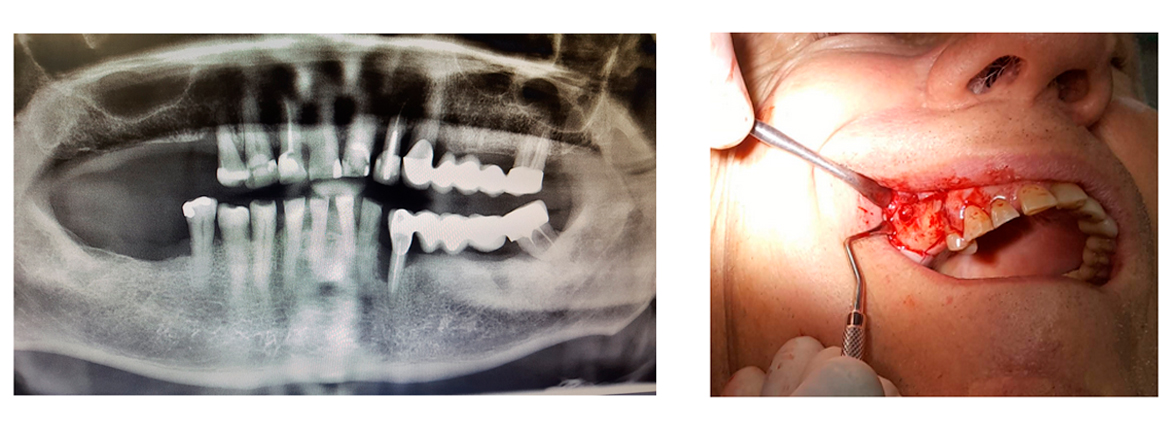

Missing teeth on the upper right side and also asked for the old bridge renewal on the left together with a correction on malposition tooth in front.

Sinus lifting was performed simultaneously with implantation. (Syntoss Bone Graft, DSI Premium Implants, DSI Silk 5.0 sutures). After a four-month recovery period, trepan open implants and abutments added using a direct impression technique.